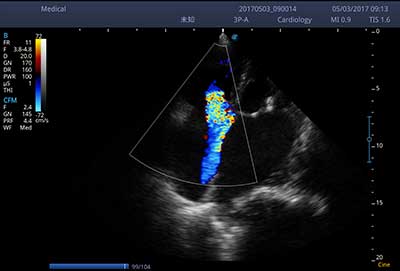

E3便携式彩色多普勒超声诊断系统拥有专业超声技术平台、高度集成化的硬件模块和结构设计、简便的操作流程、支持三探头接口全激活,兼顾了优质图像、轻便机身以及台便两用的临床使用需求。无论在常规超声科门诊检查,还是在急诊、麻醉、ICU、户外等各种应用场景。都能给您带来流程的操作体验。

• SR Flow 高分辨率血流